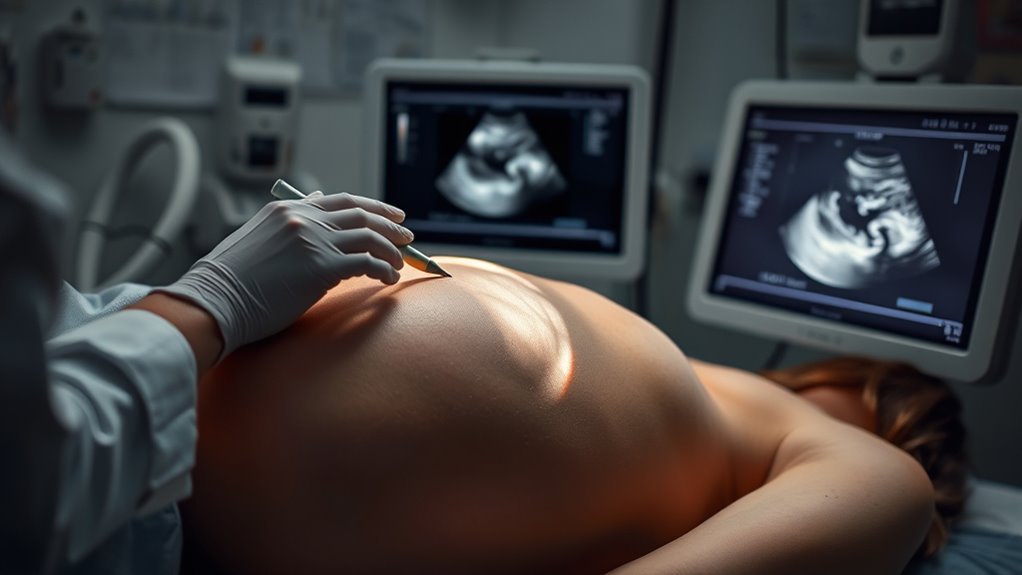

Are you curious about how doctors check the health of your developing baby? One of the first steps is usually genetic screening, which helps identify potential genetic conditions or abnormalities early on. These screenings often involve a simple blood test combined with a detailed ultrasound scan. The ultrasound scan uses high-frequency sound waves to create images of your baby inside the womb, giving your healthcare provider a clear view of growth, movement, and physical development. It’s a non-invasive way to monitor your baby’s progress and detect any potential issues.

Ultrasound scans are usually performed at various stages of pregnancy, with the most common being the nuchal translucency scan around 11 to 14 weeks and the detailed anatomy scan at 18 to 22 weeks. During these scans, your technician will move the transducer over your abdomen to capture images of your baby. The ultrasound provides crucial information, such as the baby’s heartbeat, movement, and position. It also measures the size of the fetus, ensuring proper growth, and checks the placenta’s location. This imaging can reveal potential issues like fluid buildup, structural abnormalities, or signs of miscarriage risk.

While genetic screening offers insights into your baby’s genetic makeup, ultrasound scans give you a visual confirmation of physical development. Together, these tests provide an all-encompassing picture of your baby’s health, helping your healthcare provider recommend any necessary follow-up or interventions. They’re both safe and essential tools to keep you informed and prepared throughout your pregnancy.